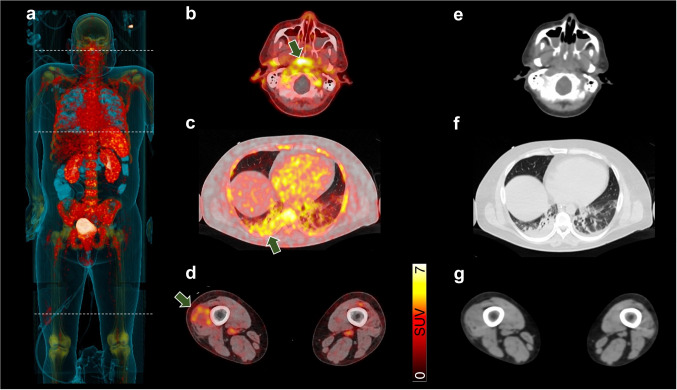

We herein report on a 37-year-old male which suffered from severe pneumonia requiring mechanical ventilation due to acute infection with severe acute respiratory syndrome coronavirus type 2 (SARS-CoV-2; COVID-19). Despite optimal anti-inflammatory treatment, the patient’s condition further deteriorated, leading to elevated inflammatory blood-based biomarkers, septic shock, and persistent temperature above 40 °C. Inflammatory-directed, whole-body positron emission tomography/computed tomography (PET/CT) targeting C-X-C motif chemokine receptor 4 (CXCR4) was scheduled to identify sites of inflammation, including the lung and distant sites of disease. In addition, previous studies investigating neutrophils also rendered CXCR4 as a potential target in severe cases [1]. After injection of CXCR4-targeting [68Ga]Ga-PentixaFor, increased radiotracer accumulation was noted in the bone marrow and spleen on maximum intensity projection (a), indicating hematopoietic activation. Additional CXCR4-expressing, inflammatory foci were identified on transaxial PET/CT in the pharyngeal/palatine tonsils (b), along with right-dominant bilateral pneumonia (c), and in the distal right thigh (d, green arrows), which may be partially explained by intramuscular inflammation. On transaxial CT (e–g), only pulmonary involvement was recorded.

There is increasing evidence on a multisystem inflammatory component in the context of SARS-CoV-2 [2] and thus, a PET-based whole-body read-out may provide relevant information on the current status quo. In this regard, [18F]FDG PET has already been applied in an acute setting after SARS-CoV-2 infection, but its challenging image protocol including prolonged fasting may hamper its more widespread adoption for emergency cases [3], in particular in patients that require glucose containing medication on intensive care units. The CXCR4-targeting radiotracer [68Ga]Ga-PentixaFor, however, has already been used in various infectious and inflammatory scenarios [4–6], as it allows to visualize CXCR4 expression on infiltrating leukocytes [7]. Relative to [18F]FDG, no further patient preparation is needed, thereby providing fast implementation in clinical routine [8]. Of note, chemokines are crucially involved in the inflammatory immune response after respiratory SARS-CoV-2 infection, in particular in severe cases. In those high-risk individuals, CD10LowCD101− CXCR4+ neutrophils have been identified, with a significant accumulation in blood and lungs [1], in a manner similar to the herein presented case (a, c). In addition, [68Ga]Ga-PentixaFor also revealed distant inflammatory foci in the thigh (d) and thus, CXCR4-targeted PET may also allow to provide a read-out of chemokine-induced hyperinflammation even in distant sites of disease. Differential diagnosis of this uptake, however, may also include accidental injury caused by daily patient care. Further studies to determine the intensity of radiotracer uptake relative to severity of the disease, the impact on patient management, the predictive potential of the PET signal for adverse outcome, or PET-based assessment of organ crosstalk (e.g., between the spleen and foci) are warranted. Such investigations, however, should not be limited to [68Ga]Ga-PentixaFor, but also include other inflammatory-targeted radiotracers, which also does not require challenging patient preparation [9].